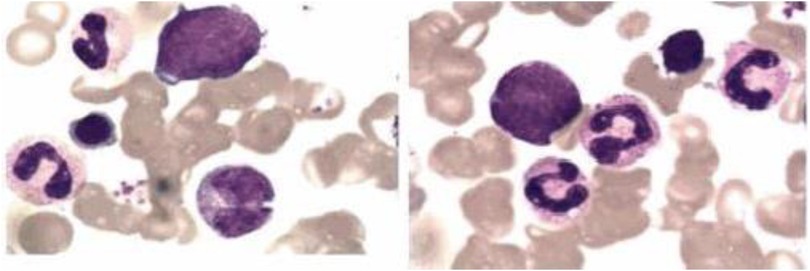

Extensive infectious workup was negative, including anti-streptolysin O, Epstein–Barr virus, respiratory pathogens, parvovirus B19, and Mycoplasma pneumoniae. Imaging of the lower limbs revealed bone marrow edema and soft tissue swelling involving both distal femurs (Figure 1), the proximal left tibia, and both ankles. Chest CT showed enhanced lung markings, while abdominal and pelvic CT revealed pneumatosis of the stomach and colon. Bone marrow cytology showed 21% erythroid precursors (Figure 2), predominantly at the intermediate and late stages, with mild anisocytosis among mature erythrocytes.

Microscopic image showing various blood cells stained for analysis. Some cells appear with dark purple nuclei, while others are light stained, indicating different cell types and structures.

Figure 2. The bone marrow analysis of pediatric patients with majeed syndrome reveals that erythroid cells constitute approximately 21% of the total bone marrow cellular composition, predominantly comprising intermediate and late-stage erythroblasts. Additionally, the mature erythrocytes exhibit anisocytosis.